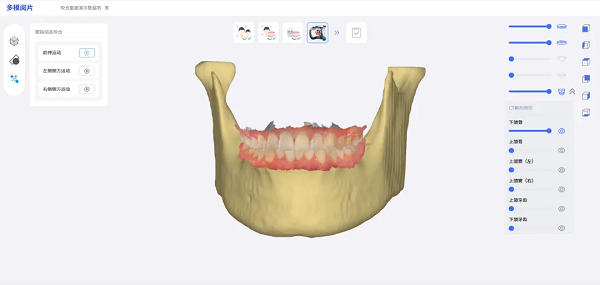

针对复杂病例,在种植修复整体设计的关键环节,菲森虚拟颌架方案实现了无模数字化流程突破。该方案可覆盖70%加工厂端病例设计,仅需椅旁快速采集口扫多咬合数据,AI即可自动拟合并提供相关参数,无需传统面弓与实体模型,便能以高精度指导个性化修复体设计,无缝衔接至设计软件。